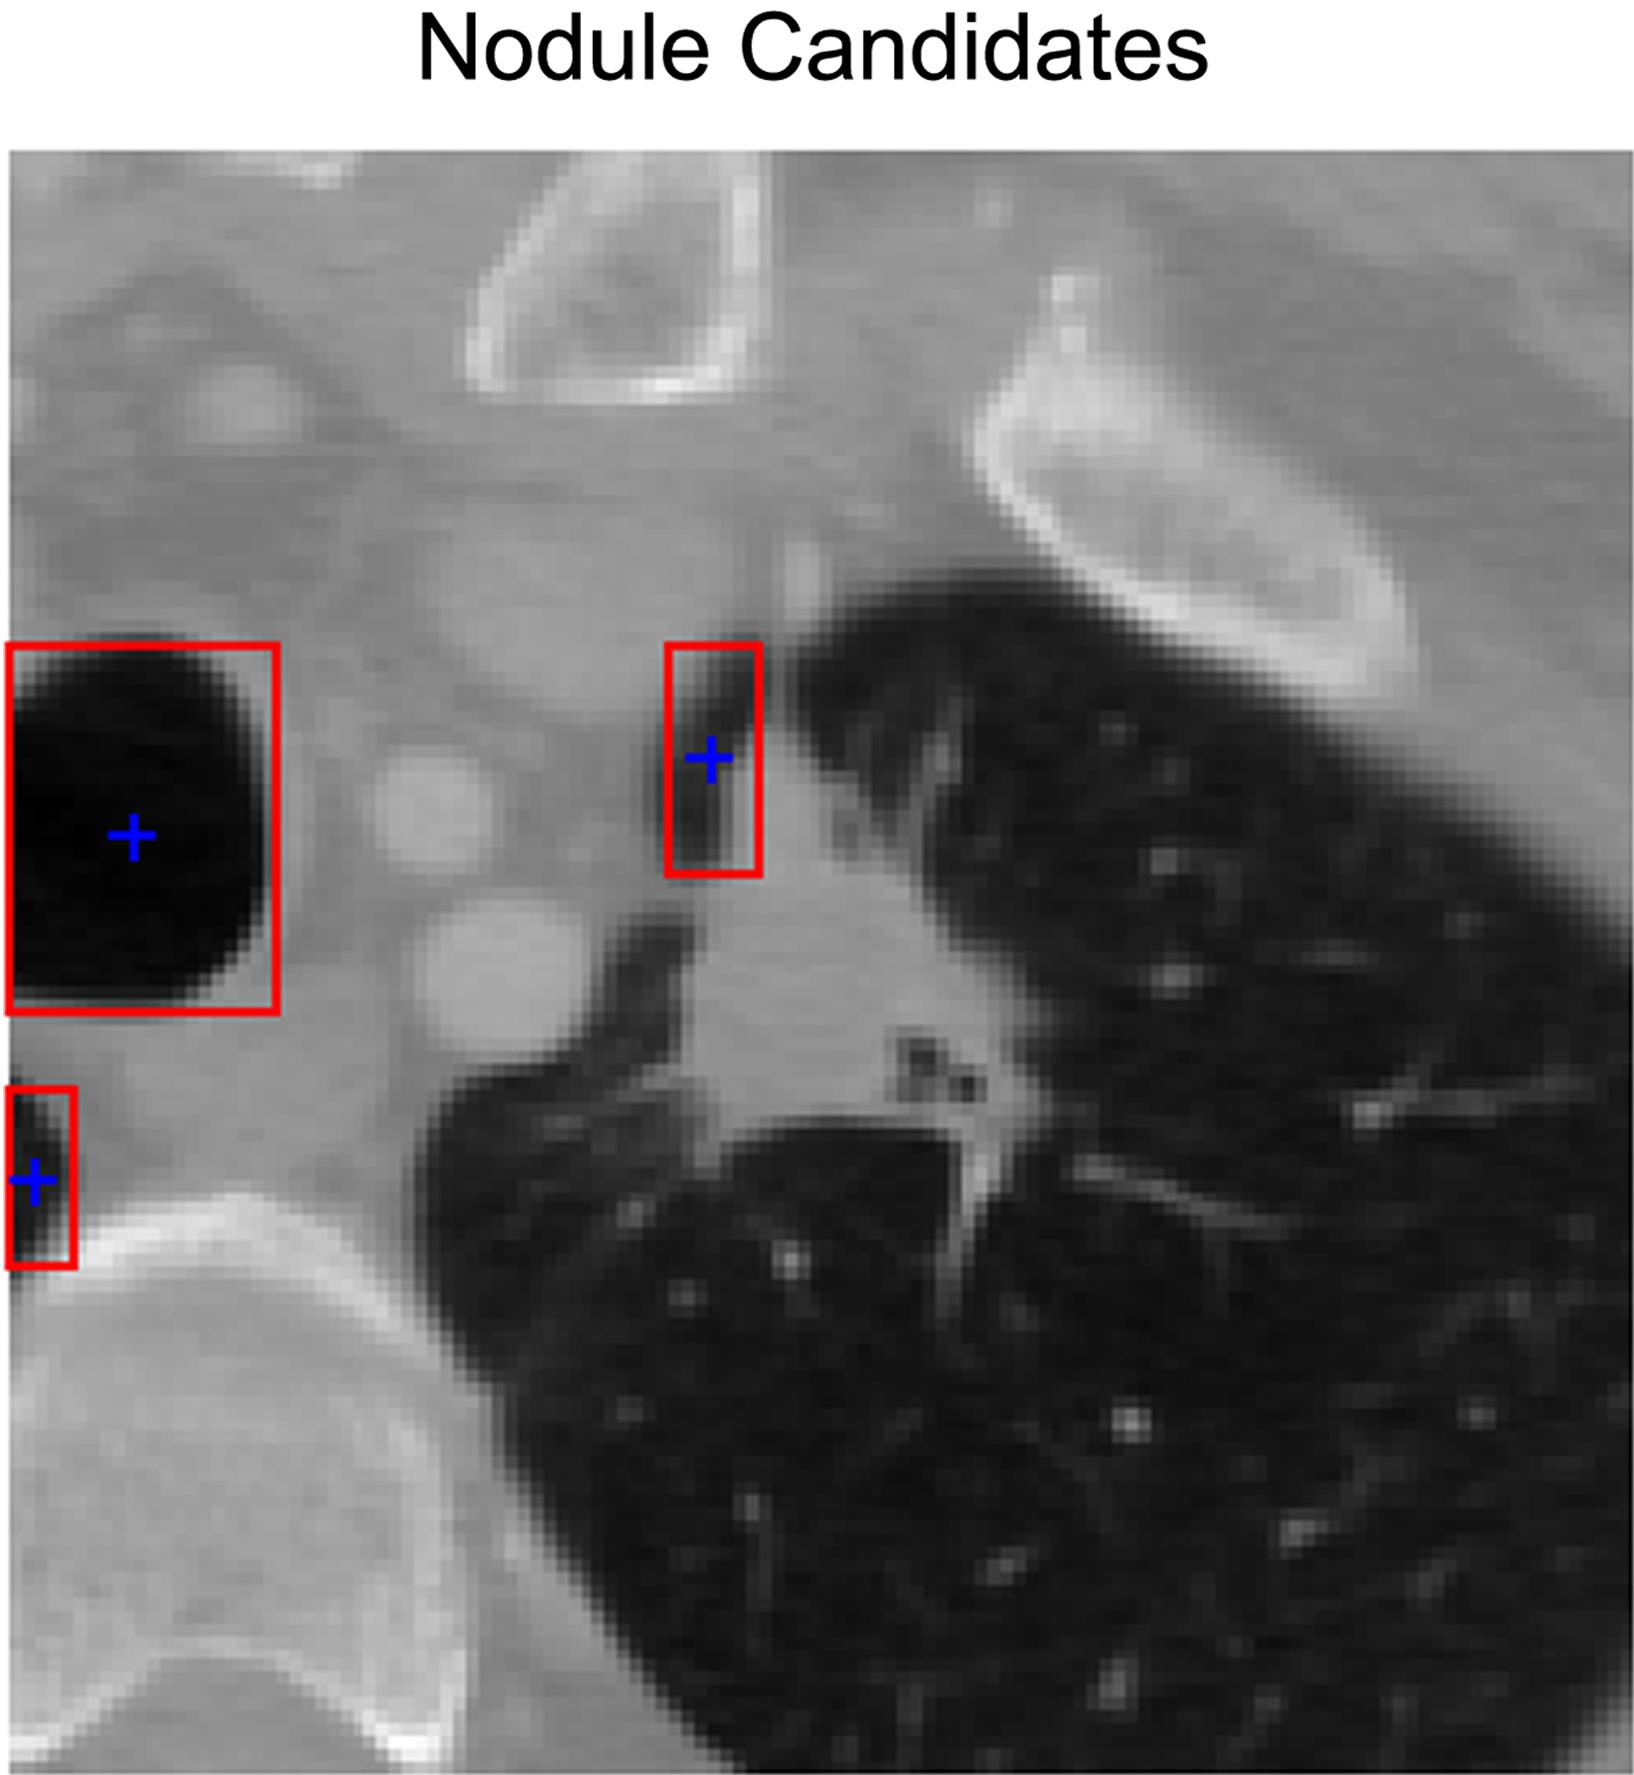

This process effectively reduced the number of detected regions. For instance, in the example shown in Figure 6, the number of labeled regions decreased from twelve to five after applying the filtering and morphological refinement steps. The final set of nodule candidates obtained through the proposed method is presented in Figure 6.

Illustration of the nodule candidate automatically detected by the proposed algorithm classification results.

Fig. 6  Illustration of the nodule candidate automatically detected by the proposed algorithm classification results.